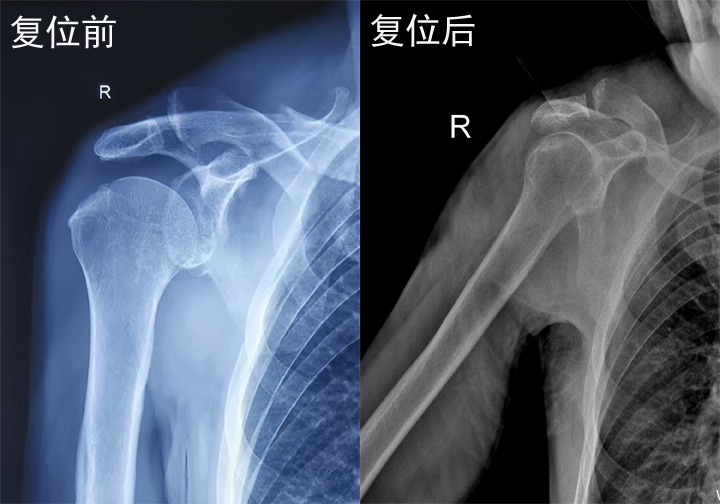

梁氏正骨-梁光兴正骨案例